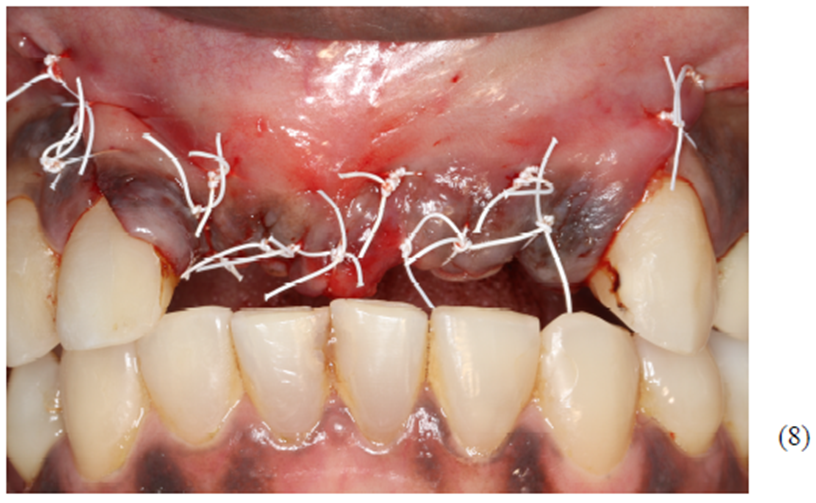

Foram colocados dois gramas de biomaterial de lenta reabsorção preenchendo toda cavidade até a delimitação da cabeça dos parafusos (Figuras 5 e 6). Antes do fechamento completo da ferida cirúrgica, colocamos membranas de PRF para auxílio na reparação tecidual e proteção do material de enxerto (Figura 7). Para fechamento da ferida cirúrgica, usamos fio do tipo Cytoplast, fornecido pela Implacil De Bortoli. É de extrema importância sua utilização, pois o fio apresenta excelente elasticidade, acompanhando edema cirúrgico pós-operatório, o que diminui o risco de deiscência no pós-operatório.